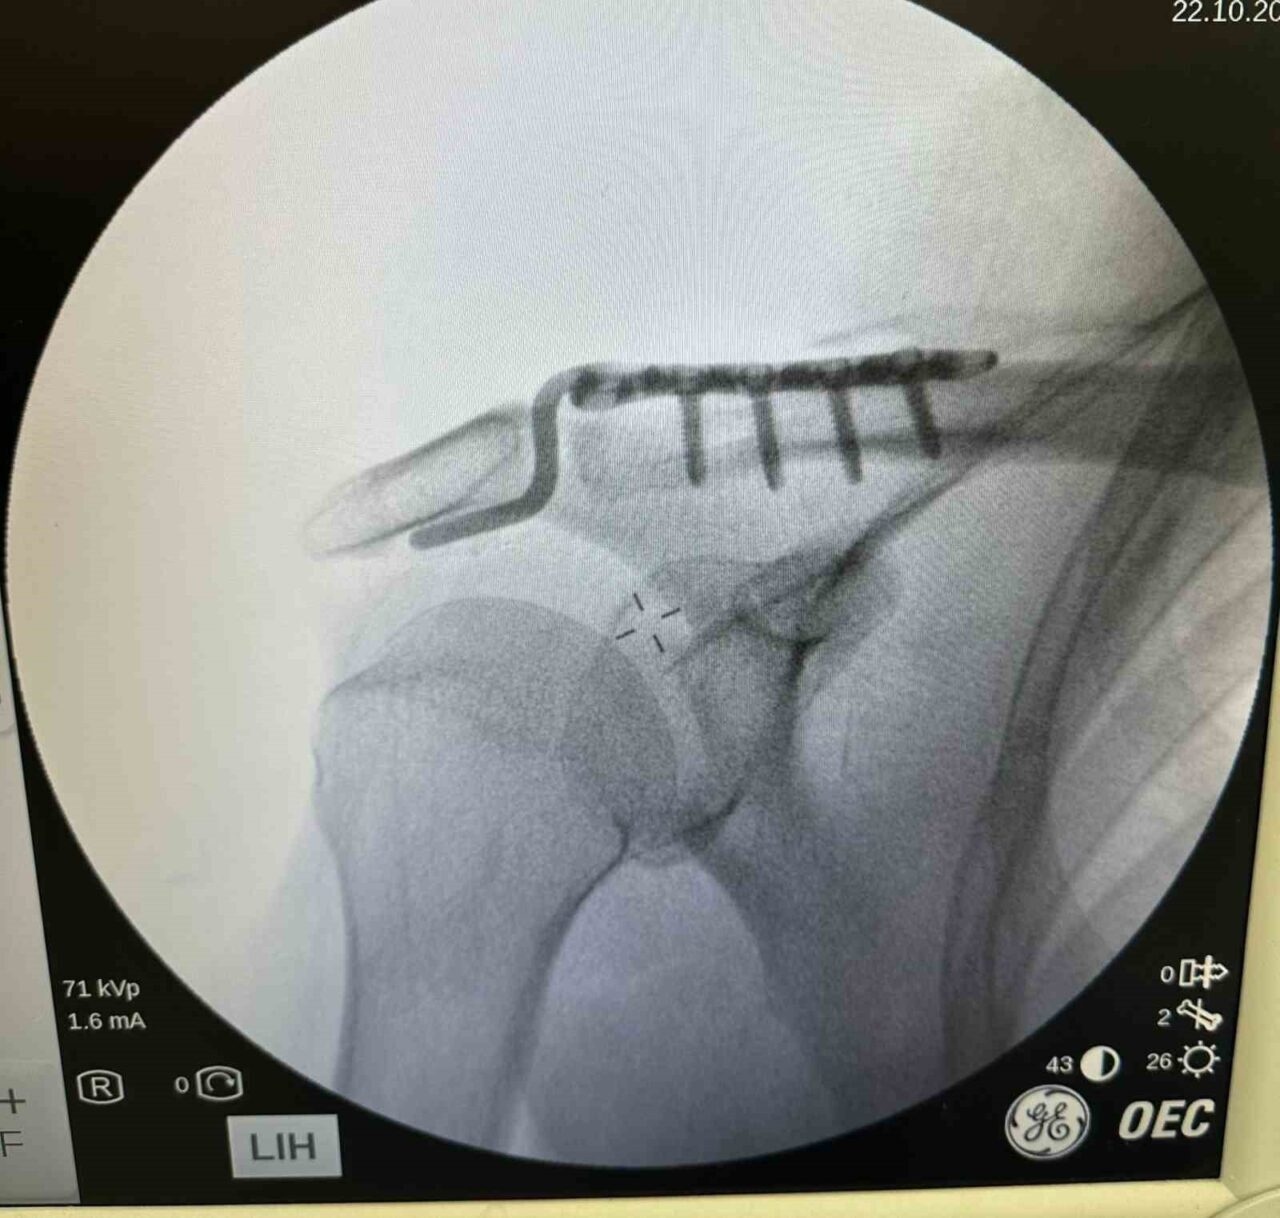

Dr. Başer, durumuyla ilgili bilgi vererek, “Hastamız omuz çıkığı nedeniyle başvurdu. Çünkü tenis oynarken düşmesi sonucunda omzunda bir problemler oluştu. Genellikle bu tür yaralanmaları genç hastalarda görüyoruz. Ancak hastamız oldukça aktiftir. İlk değerlendirmede omuz eklemi yerinde değildi. Nadir kullanılan, hastanın kemik yapısına tam uyum sağlayan bir plak ile ameliyatı gerçekleştirdik,” ifadelerini kullandı.

Ameliyat sonrasında hastanın hızla fizik tedavi sürecine başlandığını belirten Dr. Başer, “Hastamız omuz hareketlerini yavaş yavaş yapmaya başladı. Yakında kol askısından kurtulacak ve 2-3 hafta içerisinde eski performansına dönecek,” diye ekledi.